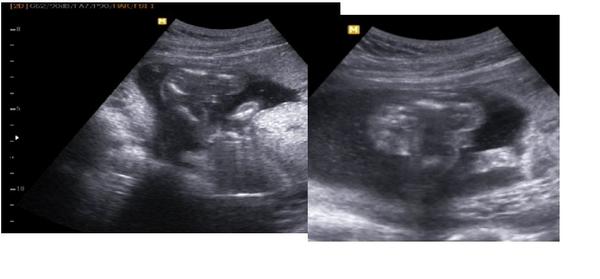

Je to holčička nebo chlapeček? Foto ultrazvuku

@rennye no podle mě to na chlapíka vypadá 😀 mám podobnou fotečku s dneška 😀

@juliemichal A ty už máš chlapečka potvrzeného? Tak to budeme pravděpodobně na stejné vlně, 3 kluci :-*. Na té tvé fotce to je označen pytlík i pindík?

@rennye ano ano už ho mám na 100% potvrzeného s dnešního screeningu 😀 na té mé fotce je jen označen pytlík 😀 pindíka měl schovaný za pupeční šňůrou 😀

@jarpa111 pindu nevidim,ale kulicky to byt muzou,ma nohy u sebe 😉 to,co jsi zakrpuzkovala je zadecek.